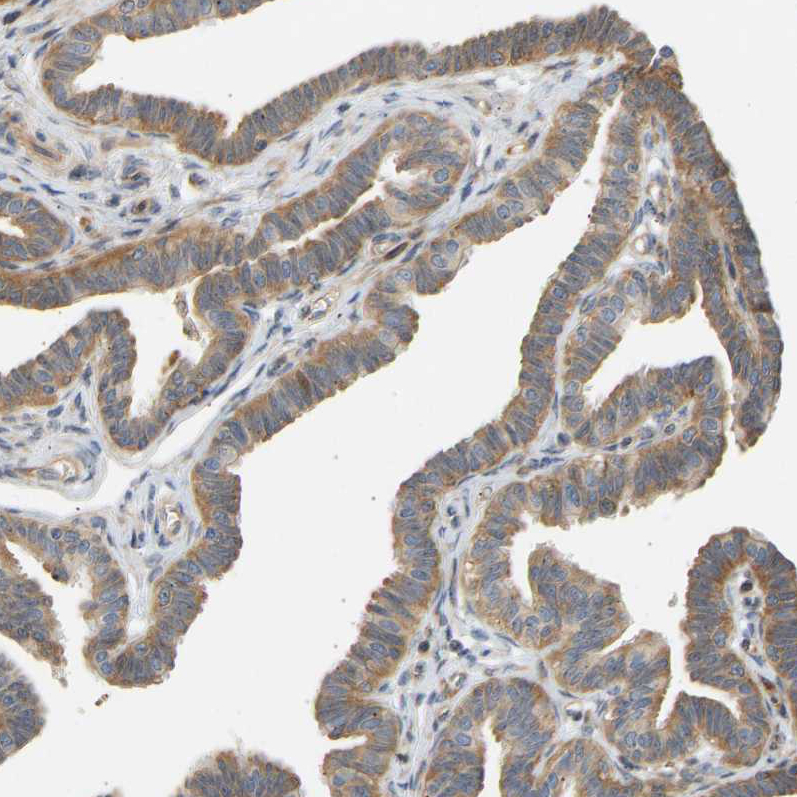

Immunohistochemical staining of human Fallopian tube shows weak to moderate cytoplasmic positivity in glandular cells.